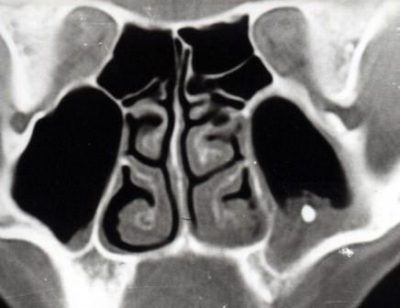

Медицинский специалист внимательно выслушивает жалобы пациента, затем осуществляет риноскопию (осмотр носовых ходов с использованием специальных зеркал). При проведении передней риноскопии обнаруживается отечная слизистая оболочка полости носа, в которой обнаруживается инородный объект. Чаще всего он располагается на переднем конце нижней носовой раковины. При выполнении передней риноскопии иногда можно увидеть движущиеся белые личинки — живые инородные объекты.

Проведение рентгенологического исследования оправдано, если инородное тело обладает рентгеноконтрастностью, то есть если предмет, застрявший в носу, содержит металлические элементы. В этом случае на рентгенограмме инородный объект будет выглядеть как темное пятно. Попытки извлечения инородного тела из носовой полости могут привести к кровотечению.

Посторонний объект может проникнуть в верхнечелюстную пазуху, что может привести к развитию синусита или заболеваний слезопроводящих путей.

Чаще всего инородное тело задерживается в нижнем носовом ходе, между носовой перегородкой и нижней раковиной. При травмах оно может попасть в средний носовой ход.

Лишь при проведении рентгеноскопии или при просмотре томографических изображений можно выявить данное заболевание.

- рентгеновское обследование, которое отображает не только наличие объекта, но и пневматизацию (присутствие воздуха);

- применение компьютерной томографии;

Также иностранные предметы в носу могут быть разделены на рентгеноконтрастные и рентгенонеконтрастные в зависимости от их видимости при проведении рентгенологических исследований. К рентгенконтрастным предметам относятся стекло, металлические объекты, косточки, фрагменты игрушек, а также пуговицы.